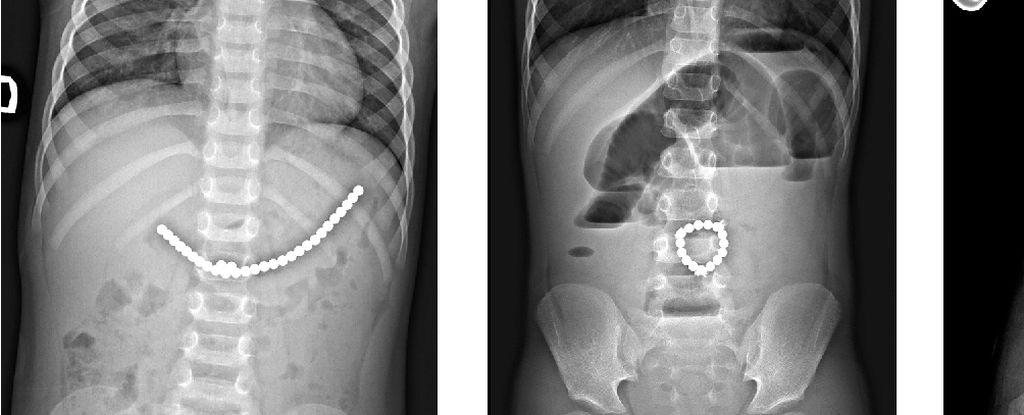

Магнитные шарики на рентгене: Интересные находки

Раздел: Картинки на заметку